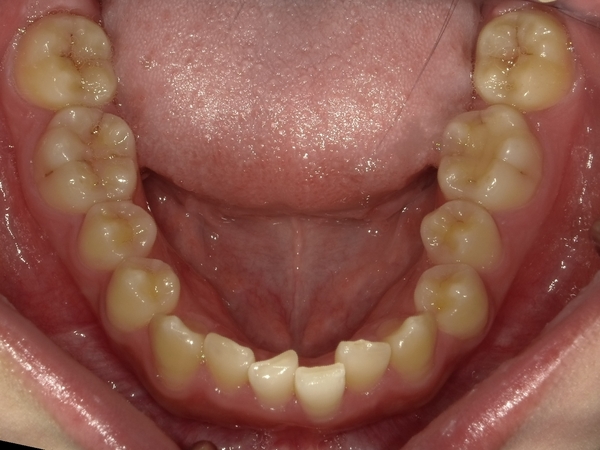

ガタガタとした歯並びや八重歯(叢生)CASE65